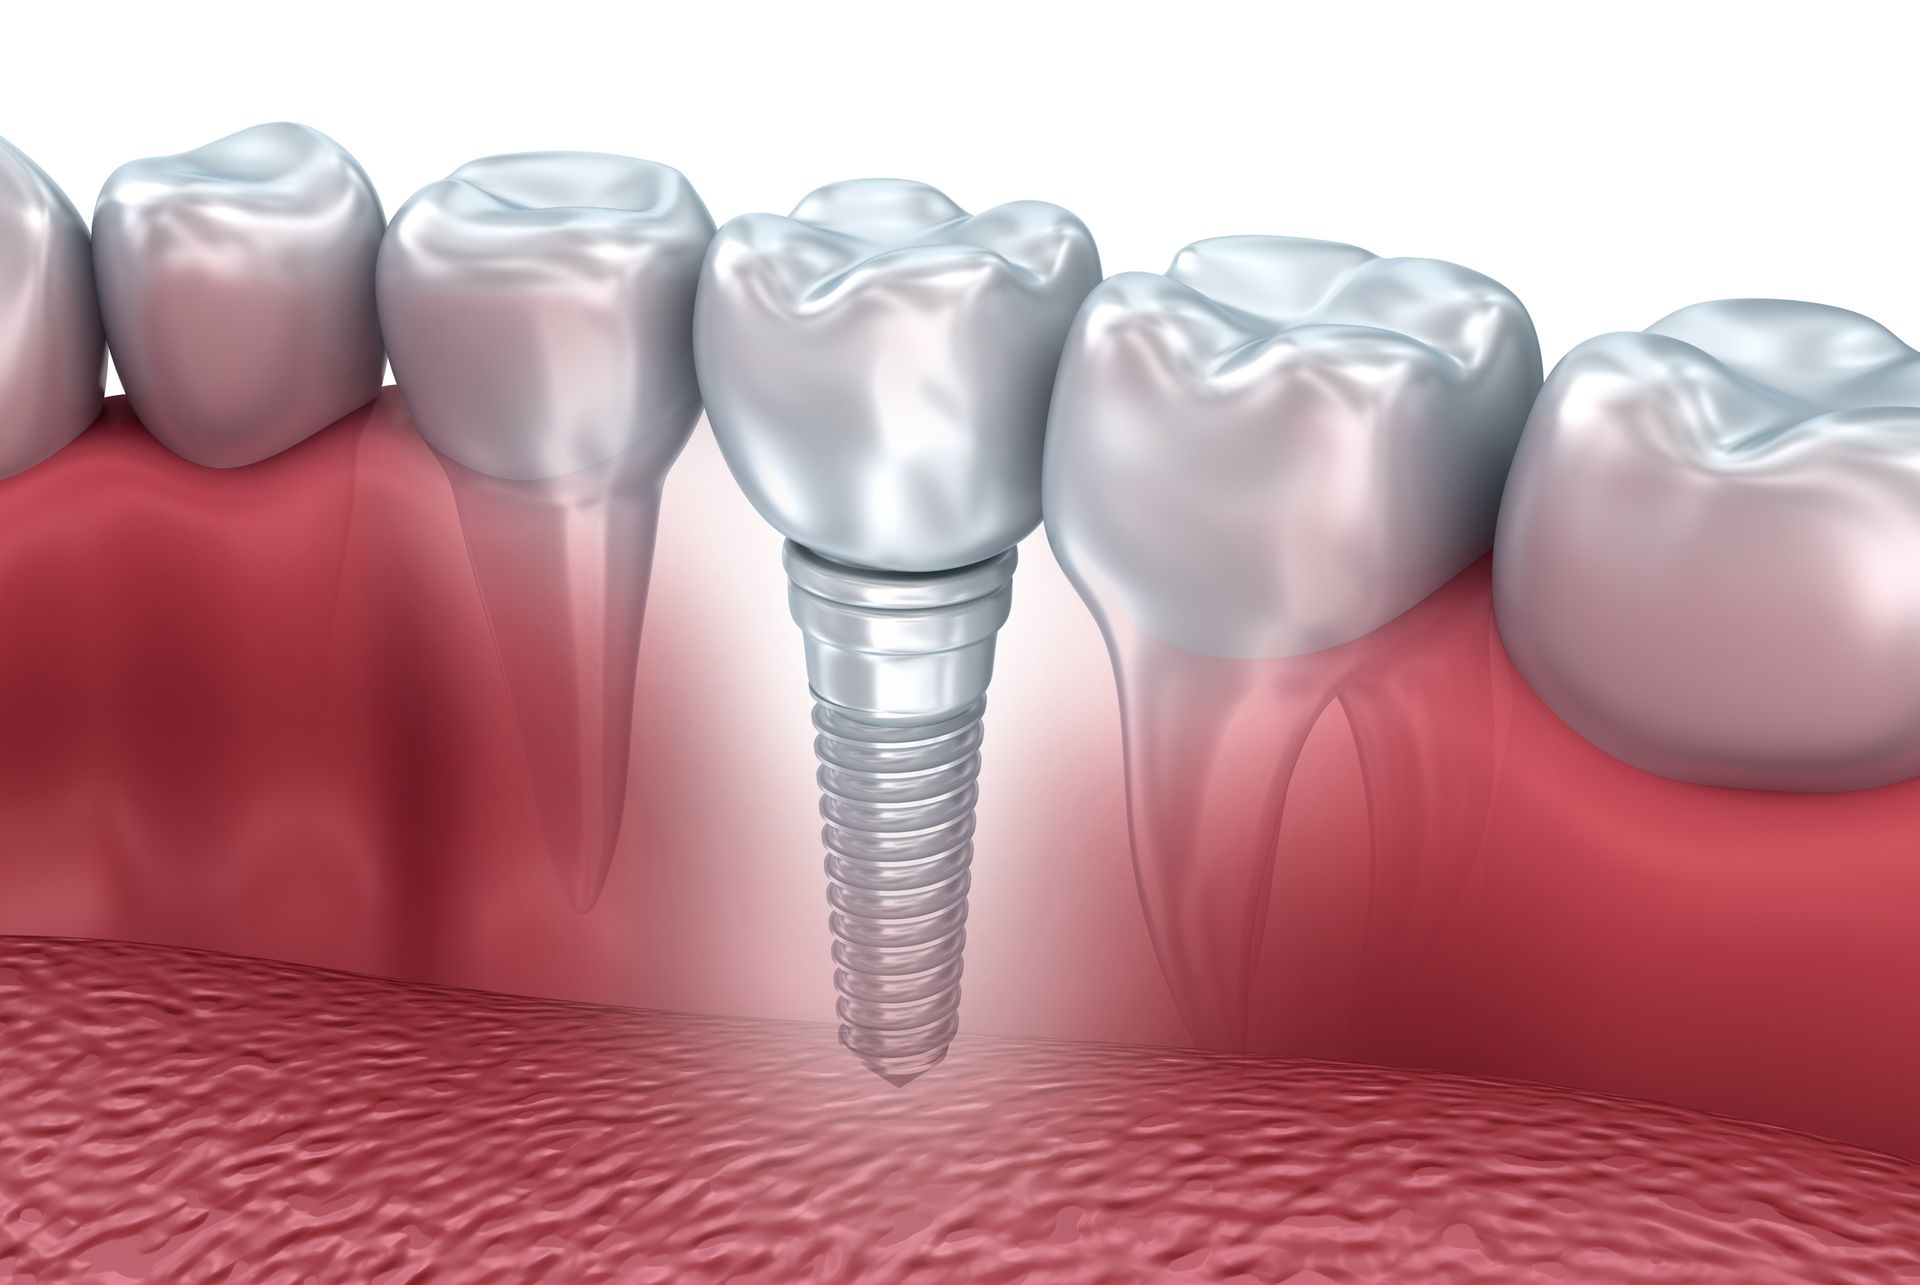

Presso il nostro studio dentistico, mettiamo a tua disposizione tecnologie odontoiatriche all'avanguardia per una vasta gamma di trattamenti, tra cui medicina estetica dentale, ortodonzia e, soprattutto, implantologia con la possibilità di carico immediato. Questo consente la riabilitazione implanto-protesica delle arcate in poche ore.